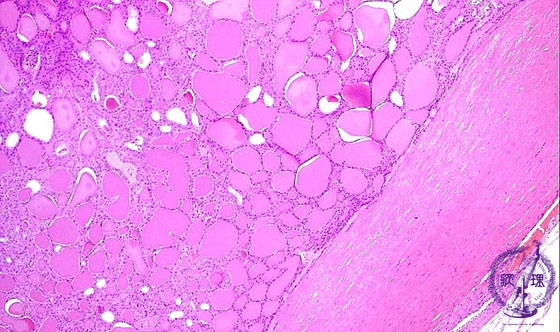

Microscopic findings (HE stain, low power view). The tumor is composed of small follicles and surrounded by thick fibrous capsule.